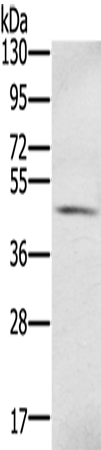

分类: 科研抗体货号: P08719别名: REPA2; RPA32; RP-A p32; RP-A p34应用: WB,IHC反应种属: Human

分类: 科研抗体货号: P08739别名:应用: WB,IHC反应种属: Human

分类: 科研抗体货号: P08718别名: MRB; AOVD3; ECSM4应用: IHC反应种属: Human

分类: 科研抗体货号: P08735别名: S100PBPR应用: WB反应种属: Human

分类: 科研抗体货号: P08716别名: Trif; HSD34; RNF36; HSD-34应用: IHC反应种属: Human, Mouse, Rat

分类: 科研抗体货号: P08734别名: MIG9应用: WB反应种属: Human

分类: 科研抗体货号: P08715别名:应用: WB,IHC反应种属: Human, Mouse

分类: 科研抗体货号: P08733别名: BCMP84; S100A15应用: IHC反应种属: Human, Mouse

分类: 科研抗体货号: P08714别名:应用: IHC反应种属: Human, Mouse, Rat

分类: 科研抗体货号: P08732别名: 2A9; PRA; 5B10; CABP; CACY应用: WB反应种属: Human, Mouse, Rat